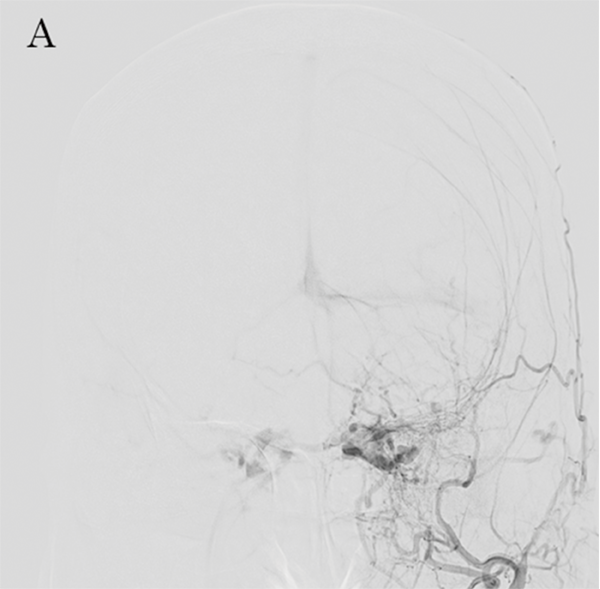

Перед проведенням трансвенозної та трансартеріальної емболізації CSdAVF за допомогою суперселективної шунтової оклюзії (SSSO)2 важливо визначити точку шунта на передопераційних зображеннях DSA (малюнок 8A та 8B).

Однак зображення DSA потрібно перевіряти багато разів.

Малюнок 8A: DSA CSdAVF, вид спереду 1

Малюнок 8B: ADSA CSdAVF, вид збоку.